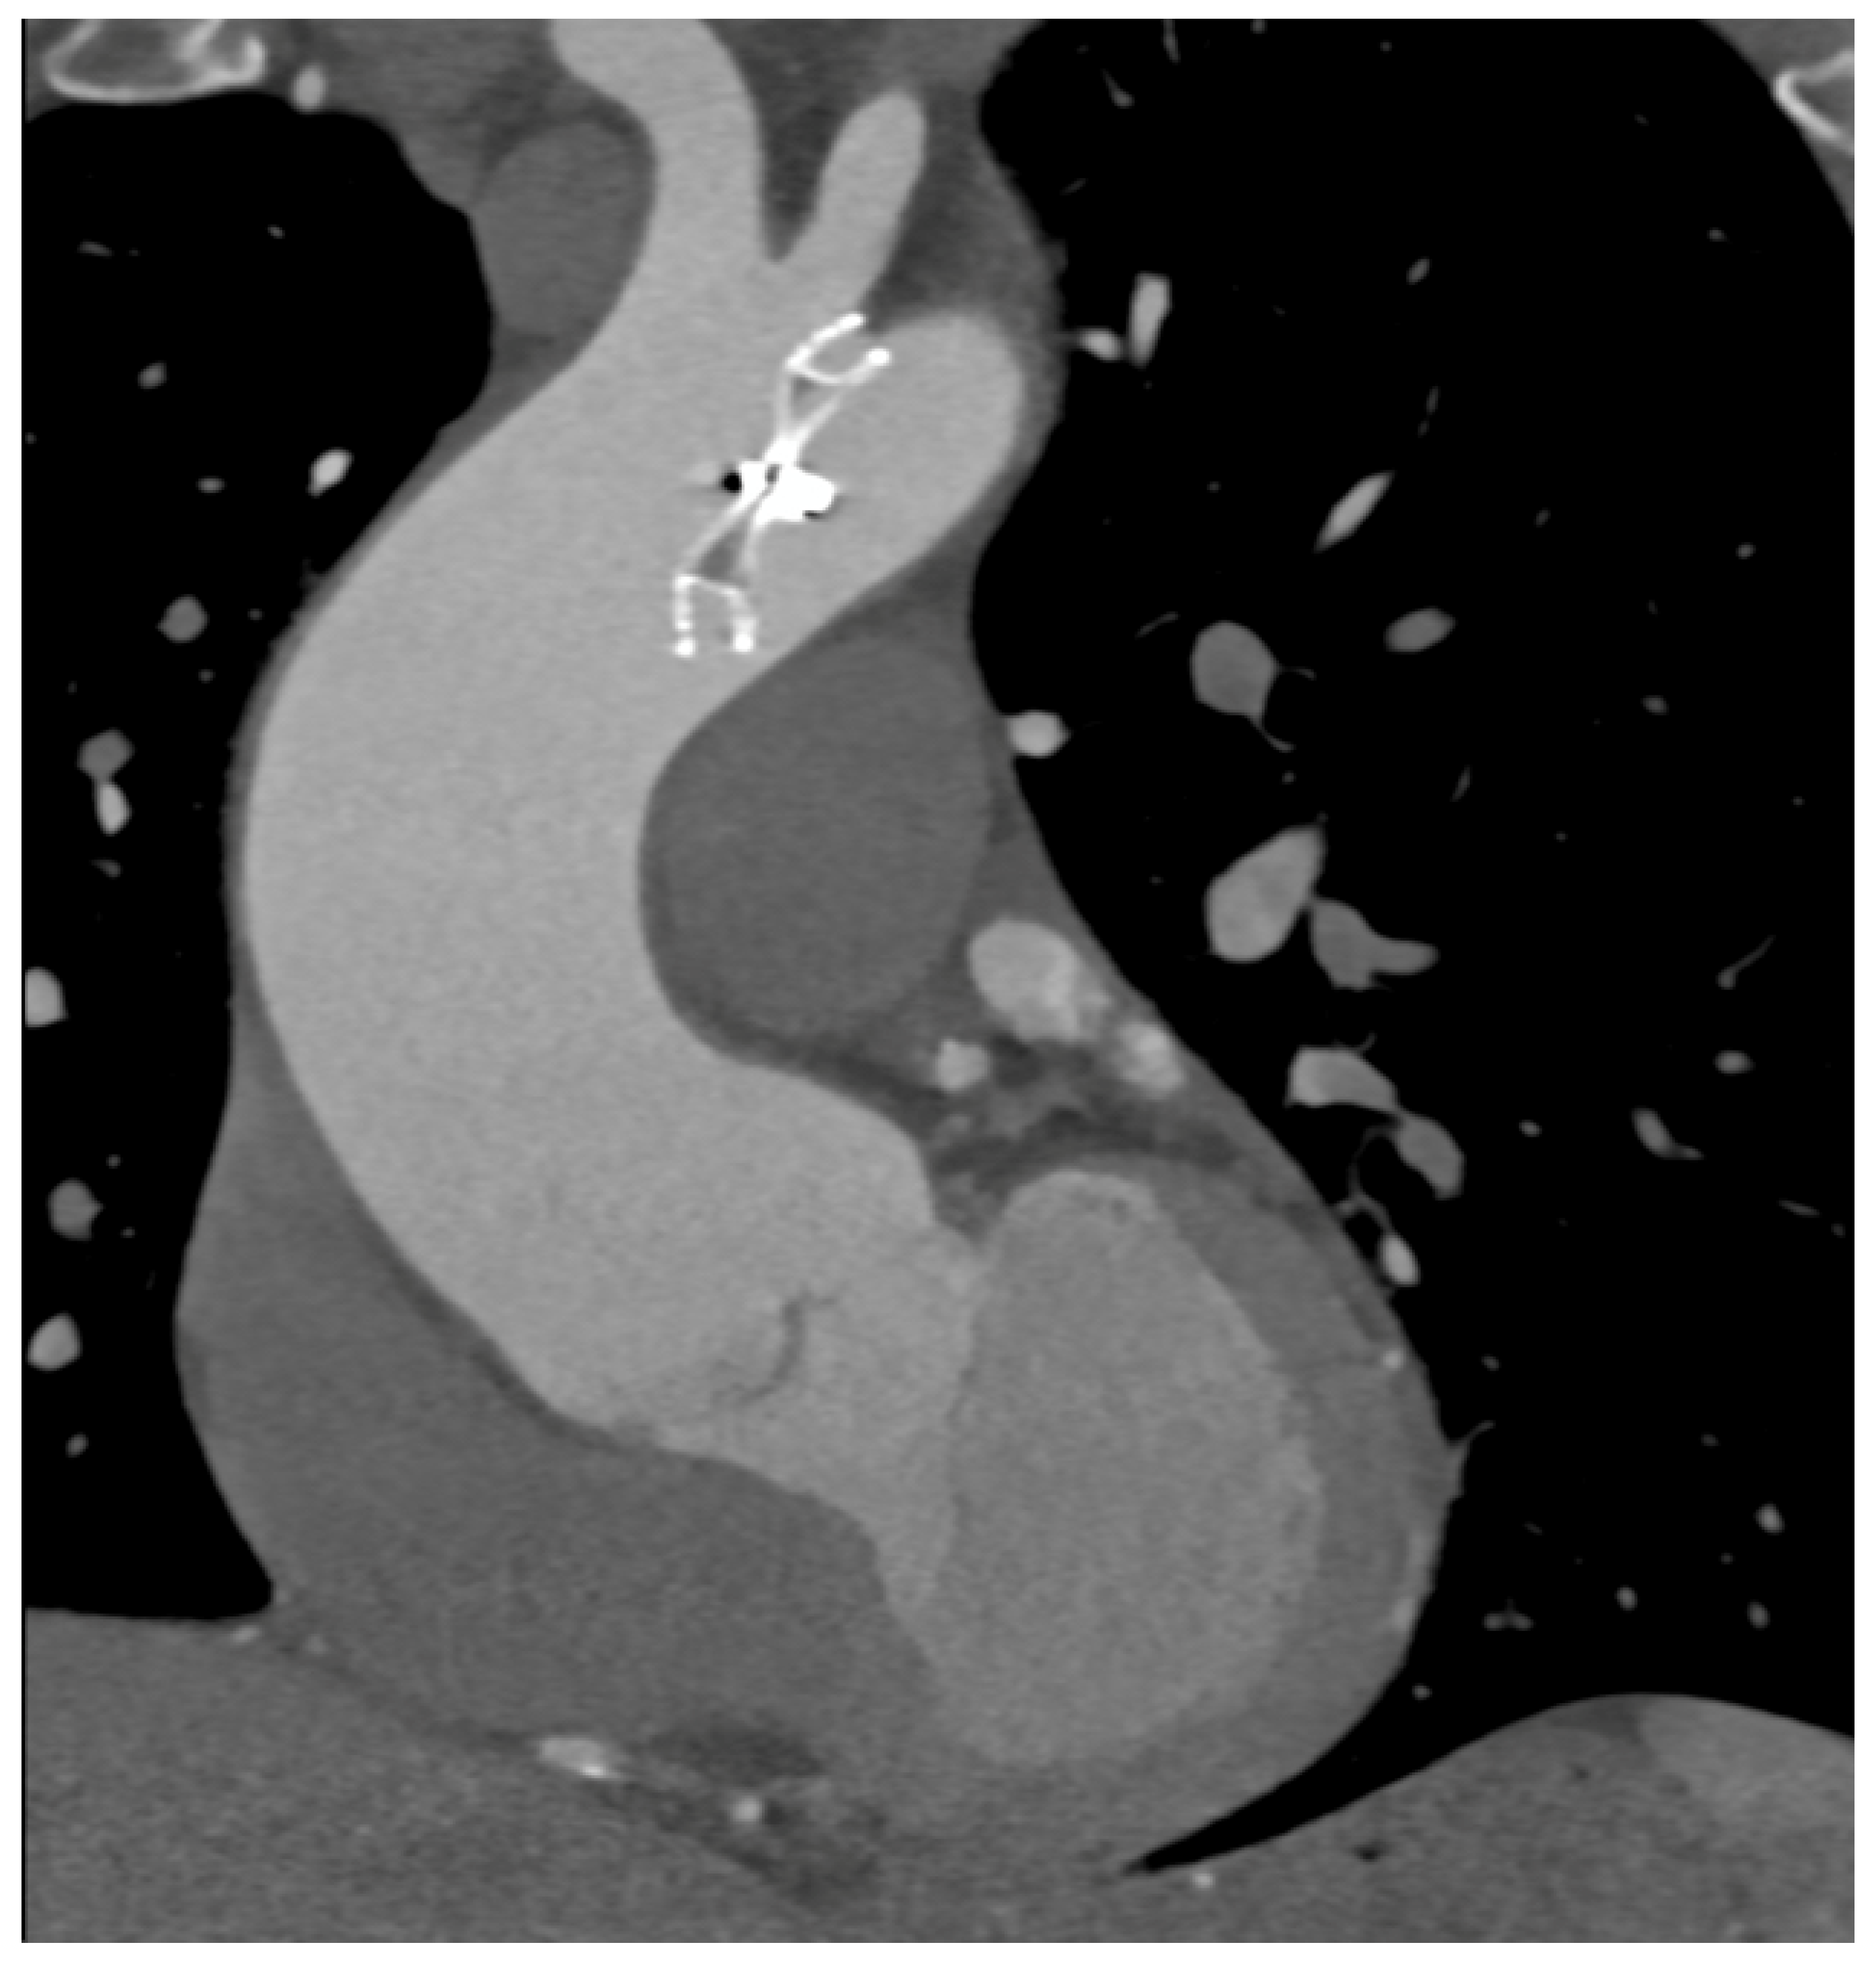

| TAVI | Transcatheter aortic valve implantation |

- Soschynski, M.; Capilli, F.; Ruile, P.; Neumann, F.J.; Langer, M.; Krauss, T. Post-TAVI Follow-Up with MDCT of the Valve Prosthesis: Technical Application, Regular Findings and Typical Local Post-Interventional Complications. Rofo 2018, 190, 521–530. [Google Scholar] [CrossRef] [PubMed]

| Dissection | PMK Compl. | Valvular Int. Compl. | PSA | Stent Compl. | Air Embolism | Occluders Compl. | Total Compl | |

| Acute Pres. | 6 | 1 | 2 | - | - | 1 | - | |

| Chronic Pres. | - | 4 | 5 | 3 | 4 | - | 1 | |

| 6 | 5 | 7 | 3 | 4 | 1 | 1 | 27 |